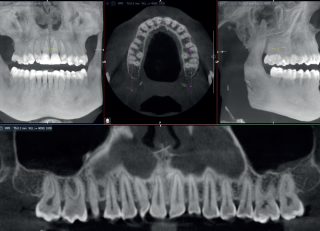

Zaawansowany detektor zastosowany w tomografie Acteon X-Mind Optima Ceph 3D gwarantuje doskonałą jakość obrazowania, niezbędną do precyzyjnej diagnostyki. Technologia ClearIQ znacząco poprawia ostrość zdjęć, a redukcja artefaktów zbieżnych zwiększa ich czytelność. Dzięki rozszerzonemu napięciu lampy do 90 kV możliwa jest lepsza penetracja tkanek, co przekłada się na wyjątkową wyrazistość struktur anatomicznych.

Elastyczny wybór pól widzenia w zakresie od 5 x 5 do 17 x 12 cm przekłada się na możliwość wszechstronnego zastosowania w ortodoncji, implantologii, chirurgii ortognatycznej oraz przy diagnostyce złożonych przypadków.